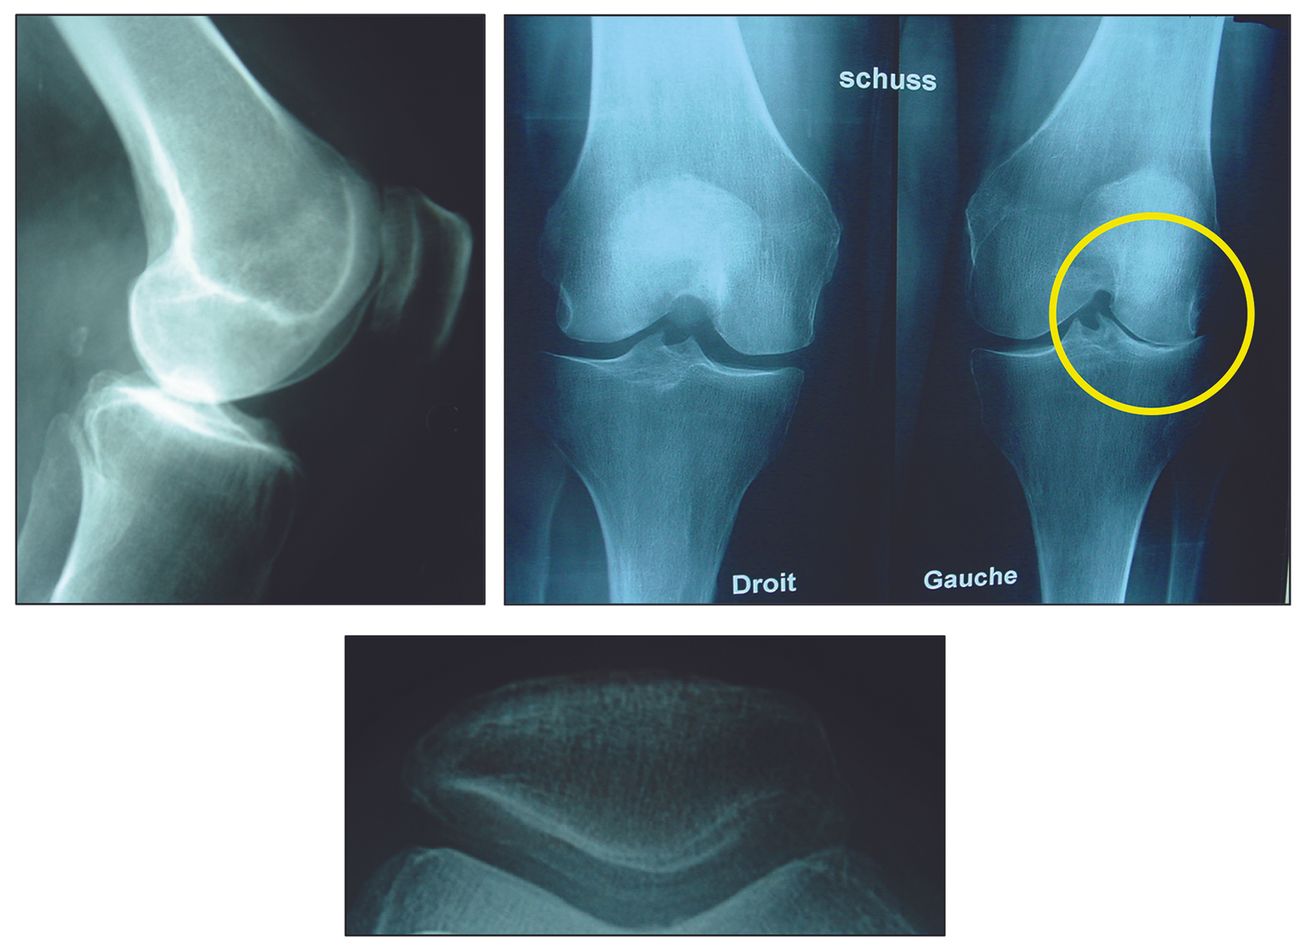

Technique Prothèses unicompartimentales latérales : le respect des indications et d’une technique rigoureuse sont les garants d’excellents résultats à long terme , Etienne Deroche Service de chirurgie orthopédique, Hôpital de la Croix-Rousse, 103 Grande rue de la Croix-Rousse, 69004, Lyon, France , Roger Badet Centre Ostéo Articulaire Fleming, 30 avenue Flemming, 38300 Bourgoin-Jallieu, France N°297 - Octobre 2020 ● 13 min de lecture